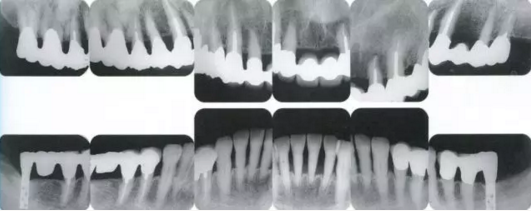

22222222222222222222222222.png

▲圖19-4

X光片。牙槽骨明顯缺失。